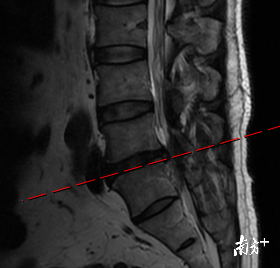

【手术|腰突压迫左腿麻痛小便困难三维导航下椎间孔腰椎减压固定融合术后缓解】术前腰椎磁共振提示L4/5椎间盘突出严重 。

经朋友介绍 , 张总来到深圳大学总医院脊柱科求诊 。 接诊的范德刚主任医师仔细询问、查体 , 发现张总左腿和会阴区皮肤感觉减退 , 左侧直腿抬高试验阳性 , 再结合腰椎磁共振检查 , 诊断为腰椎间盘突出伴马尾神经损伤(L4/5节段) 。